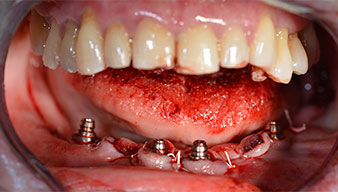

The impression and bite registration were then performed so that the dental technician could begin producing the provisional restoration immediately. This was then screwed in on the same day (Fig. 17 and 18).

Implants

Fig. 17

Fig. 18